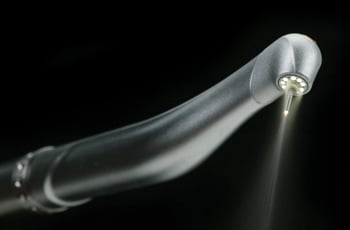

Dr. Meyers of Pinole Periodontics & Dental Implants utilizes the newest in Waterlase MD, which is a revolutionary dental device that uses a combination of laser energy and water to perform many traditional dental procedures without anesthesia or pain.

The Waterlase MD, uses a less invasive approach that conserves healthy tooth structure, which helps teeth function better and last longer.

The Waterlase MD is a revolutionary dental device that uses a combination of laser energy and water to perform many traditional dental procedures without anesthesia or pain. The Waterlase MD, uses a less invasive approach that conserves healthy tooth structure, which helps teeth function better and last longer.

When the traditional dental drill is used, heat and vibration are the major causes of most of the pain. The Waterlase MD works so fast and avoids both heat and vibration, so the tooth nerve can't respond to register pain. This means no shots or the numb feeling after the dental visit.

The Waterlase MD can also perform many soft tissue or gum procedures with little or no discomfort or bleeding.